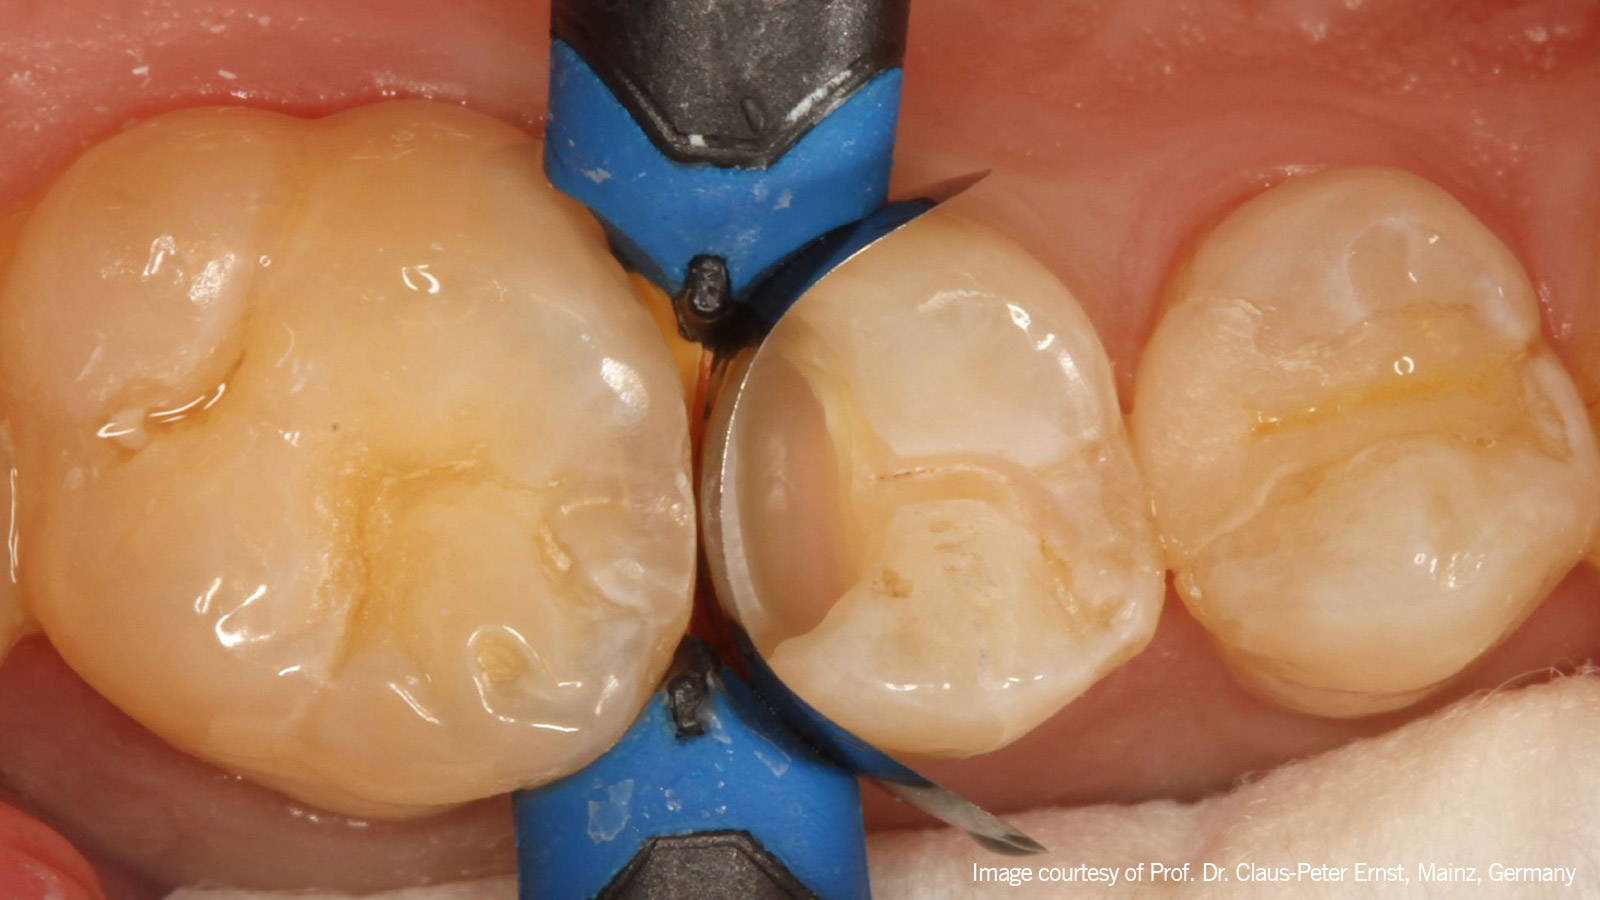

A thin layer of Venus Bulk Flow ONE

Een dunne laag Venus Bulk Flow ONE werd als basis in de caviteit geplaatst en met licht uitgehard. Daarna werd Venus Pearl ONE, een monochromatisch, pasteus composiet, stapsgewijs aangebracht om de restauratie op te bouwen.

buccal triangular ridges was placed

Eerst werd een schuine increment geplaatst om de driehoekige buccale richels te herstellen, die vervolgens met licht werden uitgehard.

rebuilding the palatal triangular ridges

De laatste increment werd geplaatst en met licht uitgehard, waardoor de driehoekige palatinale richels opnieuw werden opgebouwd.